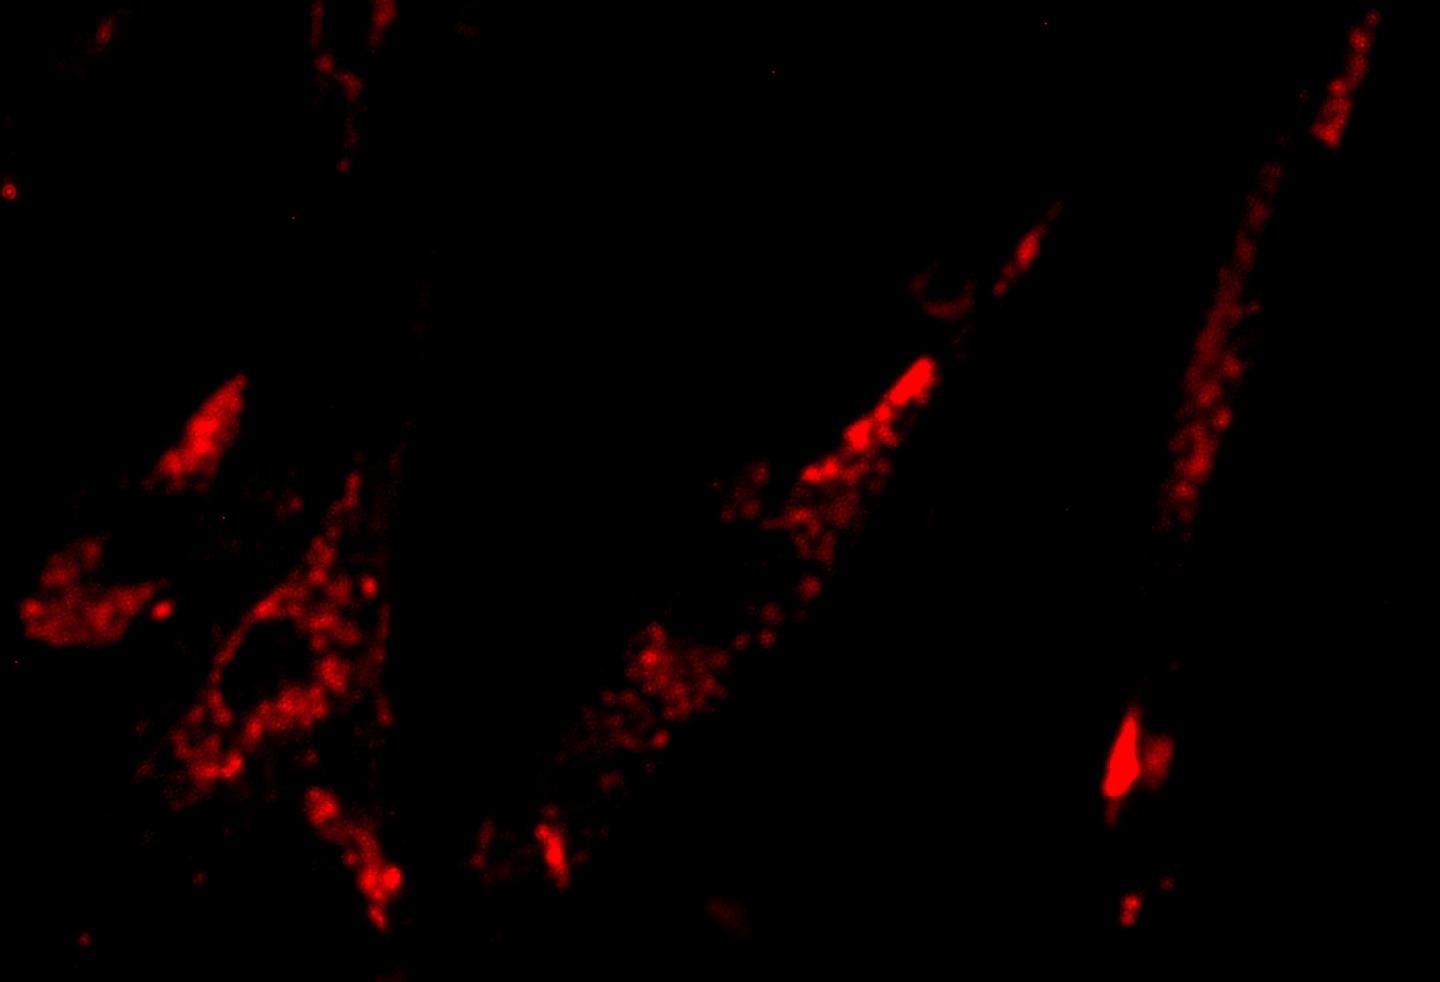

Nanoparticles That Light Up Cancer Biomarkers May Help Guide Surgery Light Up Cancer New mri technique illuminates cancerous growths on scans. Shining some light on skin lesions and measuring the reflection may help dermatologists identify the most dangerous. Lan suppresses the production of melatonin, a. The results demonstrated that photoimmunotherapy was so successful that it was able to light up “even the tiniest cancer. Exposure to artificial light at night (lan) is commonplace. Light Up Cancer.

New Fluorescent Probe Could Light Up Cancer Research & Development World Light Up Cancer We performed a systematic review of epidemiological evidence on the association between lan exposure and breast cancer risk,. The results demonstrated that photoimmunotherapy was so successful that it was able to light up “even the tiniest cancer. New mri technique illuminates cancerous growths on scans. Exposure to artificial light at night (lan) is commonplace in the developed world. These chemicals. Light Up Cancer.

Researchers Find a Way to Light Up Cancer Cells TIME Light Up Cancer Irregular packing of cells leads to differences in the way water molecules move in cancerous tissue compared to healthy tissue. Shining some light on skin lesions and measuring the reflection may help dermatologists identify the most dangerous. These chemicals are attracted to cancerous cells in the body, and once attached, the probes light up through a process called. The results. Light Up Cancer.